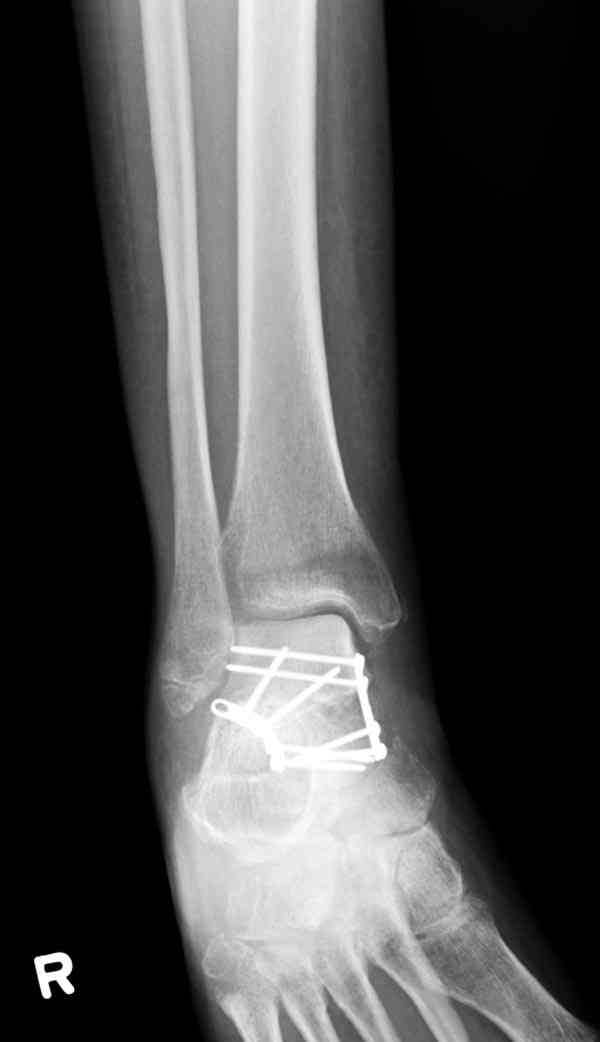

Случай с множественным оскольчатым переломом тарана оперированный из двойного доступа.

Через 2 мес.:

Через 8 мес.:

Через 14 мес.:

Для оценки состояния нужны дополнительные исследования, например

повторили рентгенограммы и доделали проекции, к единому мнению все еще не пришли

Решили не связываться с остеосинтезом, а сделать сразу берцово-пяточный блок. Снимки в приложении.

По завершении удлинения, наверно, заштифтуем.